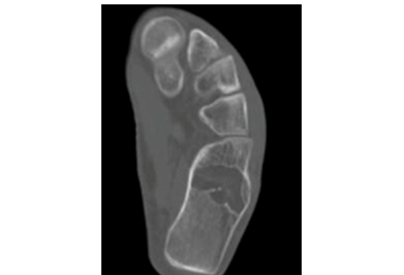

Twenty four year old male presented to us with left heel pain for nine weeks of duration. The onset of the pain was insidious and aggravated by weight bearing and prolonged standing. It was relieved with the use of analgesics and limb rest. There was no history of preceding trauma or rest pain. On examination there was no local swelling and skin changes. Deep tenderness was present over anteromedial aspect of calcaneum. Plain radiographs of the heel revealed well defined, lytic lesion in the calcaneum. Computed Tomographic scan of the same showed lytic lesion in the in the body of calcaneum just below the posterior facet. Provisional diagnosis of benign bone tumor was made and patient was planned for curettage and bone grafting.

Intraosseous lipomas are diagnosed with plain radiography and CT scan (Figure 1) (Figure 2A) (Figure 2B). Mainstay of treatment is conservative; however surgery is indicated in severe pain not responding to conservative treatment, impending pathological fracture and malignant transformation (Figure 3). Treatment for these tumors is curettage and bone grafting (Figure 4) with good prognosis.8–10

Figure 2 CT Scan of ankle showing lytic lesion in calcaneus.